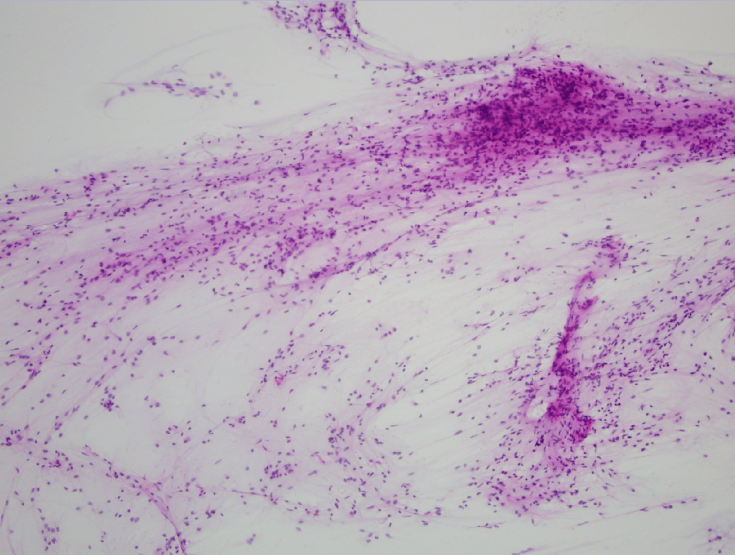

Pilocytic astrocytoma is a circumscribed glioma (WHO Grade I) commonly found in children and young adults. Characteristic features include piloid cells with long, thin, hair-like cytoplasmic processes and a myxoid background, which are both seen here in this medium power image of a cytologic smear preparation performed during intraoperative consultation.